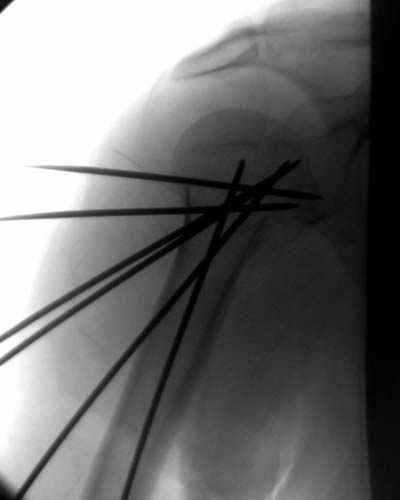

Djoldas Kuldjanov 30 Ноябрь 2004, 23:36

Случай интересный и заслуживает внимания со своей актуальностью, потому что открывать такие переломы вряд ли кому доставит удовольствие, даже тем, кто владеют АО или locking concept technique.

Учитывая отсутствие знаний о методике, хотя я очень заинтересовался, после прошлегодного доклада из ЦИТО в Ст. Петерсбурге, простота методики и отсутствие миграции спиц распологает к себе.

Интересно знать, какого диаметра спицы пригодны для фиксации?

Пока я пользуюсь методикой принятой у нас (методика Сиэтла), также перкутанный спицевой метод, только сцицы 2.8 мм с резбой на конце.

Здесь случай перелома-вывиха плеча, больному 56 лет, после "дважды" закрытой неудачной репозиции, опять же ургентно взяли в операционную, после полного общего обезболивания попытались сделать репозицию, и фиксацию провели спицами.

Больной находился в повязке, примерно напоминяющей косыночную, рекомендованы движения в локтевом суставе и маятниковые движения в плече, спицы удалены в три недели (были случаи миграции)

Больной амбулаторный, предупрежден на случай осложнения АВН головки.